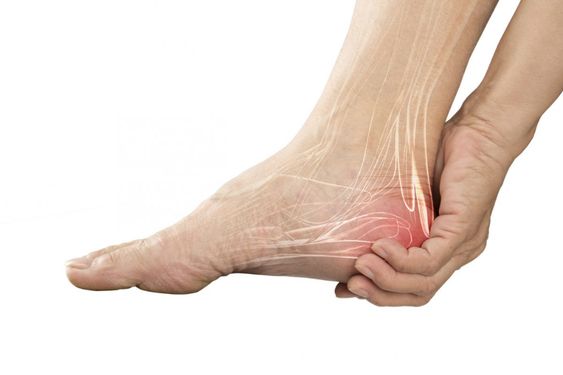

1. 아침 첫걸음 통증

- 가장 대표적인 증상으로, 잠에서 일어나 첫발을 디딜 때 발바닥에 날카로운 통증

- 움직이다 보면 서서히 완화되지만, 매일 반복되면 의심 필요